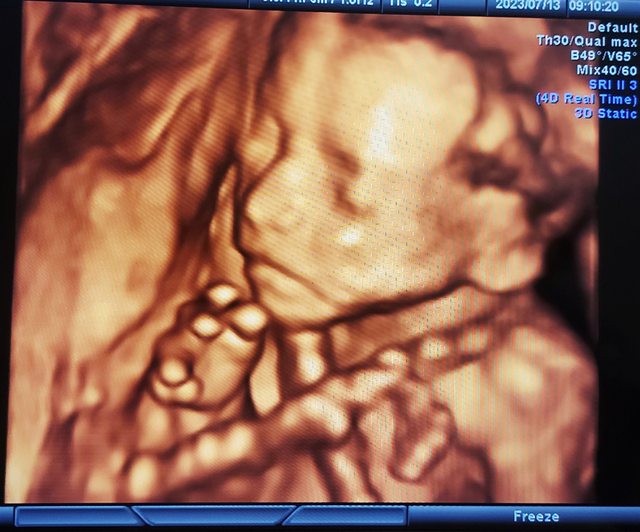

非常感謝fulin媽媽 這麼熱心的回覆我這篇文章, 讓我們知道還有其他人也是這種情況, 和後續的控制處理方法! 原文引起許多媽媽的迴響與譴責, 本來不打算做回應了, 但想了想,還是覺得出來澄清一下, 避免讓諸位媽媽們如此義憤填膺。 我和太太結婚快八年,從太太33歲開始, 做了兩次人工受孕,三次試管植入 很幸運第一次取卵就取到八顆, 有四顆4A等級, 可惜的是第一跟第二次各植入一顆4AA 都是驗孕開獎中獎,可是都空包彈。 而太太在疫情開始沒多久後 因疑似憂鬱症開始看身心科, 期間體重最瘦到157公分,37公斤。 看在家人眼裡都十分心疼。 在年初決定做第三次植入 也是下了很大的決心, 畢竟生孩子這件事是和時間賽跑, 身心科醫生也是覺得如果有了孩子, 身心狀況有可能會好轉, 因此開始了邊吃抗憂鬱的藥物, 邊做不孕症治療, 而不孕症醫生給的建議就是增重, 所以在飲食方面我們基本上是百無禁忌, 老婆想吃什麼我就盡量滿足他。 很幸運的第三次植入兩顆 終於成功著床一顆, 開始做產檢後,體重大概接近40公斤, 也有把身心科病史告知產檢醫生, 產檢醫生給我們的意見, 就是老婆懷孕最大,想吃什麼盡量吃, 畢竟有憂鬱症,體重又過輕, 孕婦的心情要好最重要,不要吃中藥就好。 因此從懷孕開始,也是聽從醫生指示 盡量滿足口腹之慾。 期間在懷孕第九週和第十週 都在某天晚上突然陰道出血 緊急送急診,所幸寶寶都正常 醫生也開了黃體素叫我們繼續吃 查了一下文獻資料,服用過多黃體素 好像也是妊娠糖尿的原因之一? 而在第二次出血後,寶寶一路平安長大, 羊水,高層次報告都沒問題 可是我老婆的孕吐一直到16週都還很嚴重, 幾乎是吃什麼就吐什麼。 醫生也是開止吐藥,少量多餐這樣。 在16週後沒有孕吐後老婆食欲突然變的很好 從六月開始體重直線上昇,43胖到51公斤, 其實我和他爸媽反而沒有擔心, 更多的是高興,因為之前真的太瘦。 產檢醫生也說這是好現像。 結果好景不常,上禮拜的妊娠糖尿確診 讓我們十分錯愕,畢竟家族沒有糖尿病史 以前健檢也都沒有紅字。 而第二第三管血的血糖濃度幾乎一樣, 加上我自己本身健檢 連續兩年碰到醫院數據誤植, 才會想上來問看看是否有病友跟我們一樣 第二小時血糖完全沒下降的。 有些博學多聞或在醫院工作的網友, 說這數據很正常,很常見。 但我自己搜尋的資料的確是找不到類似的, 也是上來問以後, 才有其他媽媽說有類似數據, 他們自己當初也是很錯愕驚恐無助。 發這篇文章, 也是有讓日後碰到相同問題的媽媽, 有跡可循,不至於像我們這樣大驚小怪 用意也是良善不是嗎? 很多版友覺得我們不珍惜這個孩子, 相信為人父母者,沒有人不珍惜自己的孩子 更何況這是媽媽經歷了各種苦難 才來到肚子裡陪伴他的寶寶。 如果真的確診了,當然就是飲食控制 我也沒有說過不配合醫生營養師, 只是提出自己對報告的疑問, 畢竟院方也很少會跟你解釋那麼多, 提出數據的問題也是跟你說 中了就是中了,控制飲食就好了。 今天在寶媽版發這篇文章, 雖然收到不少冷嘲熱諷, 但慶幸的是還是有許多熱心媽媽們 解答了我的疑惑, 不論是和我們一樣數據的病友, 或是告訴我葡萄糖耐受度的前輩, 還有血糖曲線峰值可能不在第一小時 是在1.5小時,這都是非常好的回應和答案 在這邊由衷的感謝大家。 附上一張寶寶高層次的帥照, 希望他可以平安的來到媽媽身邊陪伴我們 https://i.imgur.com/Ns2W6U1.jpg

dreadnought : 辛苦你們了 祝平安順利 超音波照好清楚啊08/09 19:17

hiayu : 寶寶鼻子好挺 08/09 22:52

kagaya : 這張照片……圍著脖子那是臍帶嗎? 08/09 23:00

candyrainbow: 寶寶好配合,輪廓好清晰,高層次照的太清楚了吧,這 08/09 23:19

candyrainbow: 錢沒有白花XD (我兒都一直擋,沒有這個小確幸XD)08/09 23:19

candyrainbow: 。祝福媽媽寶寶都平安健康!08/09 23:19

xchangex : 辛苦了。寶寶真的有帥! 08/10 00:56